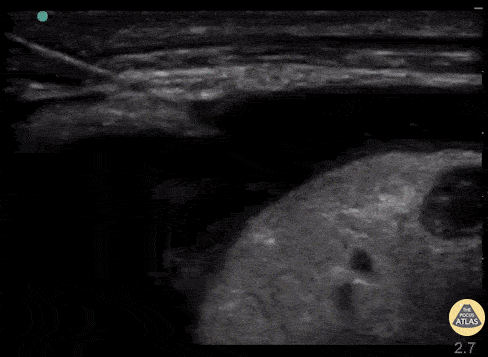

Real time US for thoracentesis. Linear probe in the longitudinal plane and thoracentesis needle approaching off plane. The needle is visualized as it transverses the layers into the pleural space while the provider performs negative aspiration. Ultrasound image courtesy of thepocusatlas.com